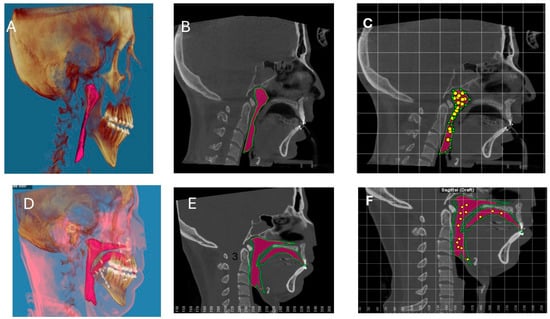

2.1. Surgical Procedures

2.2. Bilateral Sagittal Split Osteotomy (BSSO)

4.2. Advantages of Wedge Osteotomy